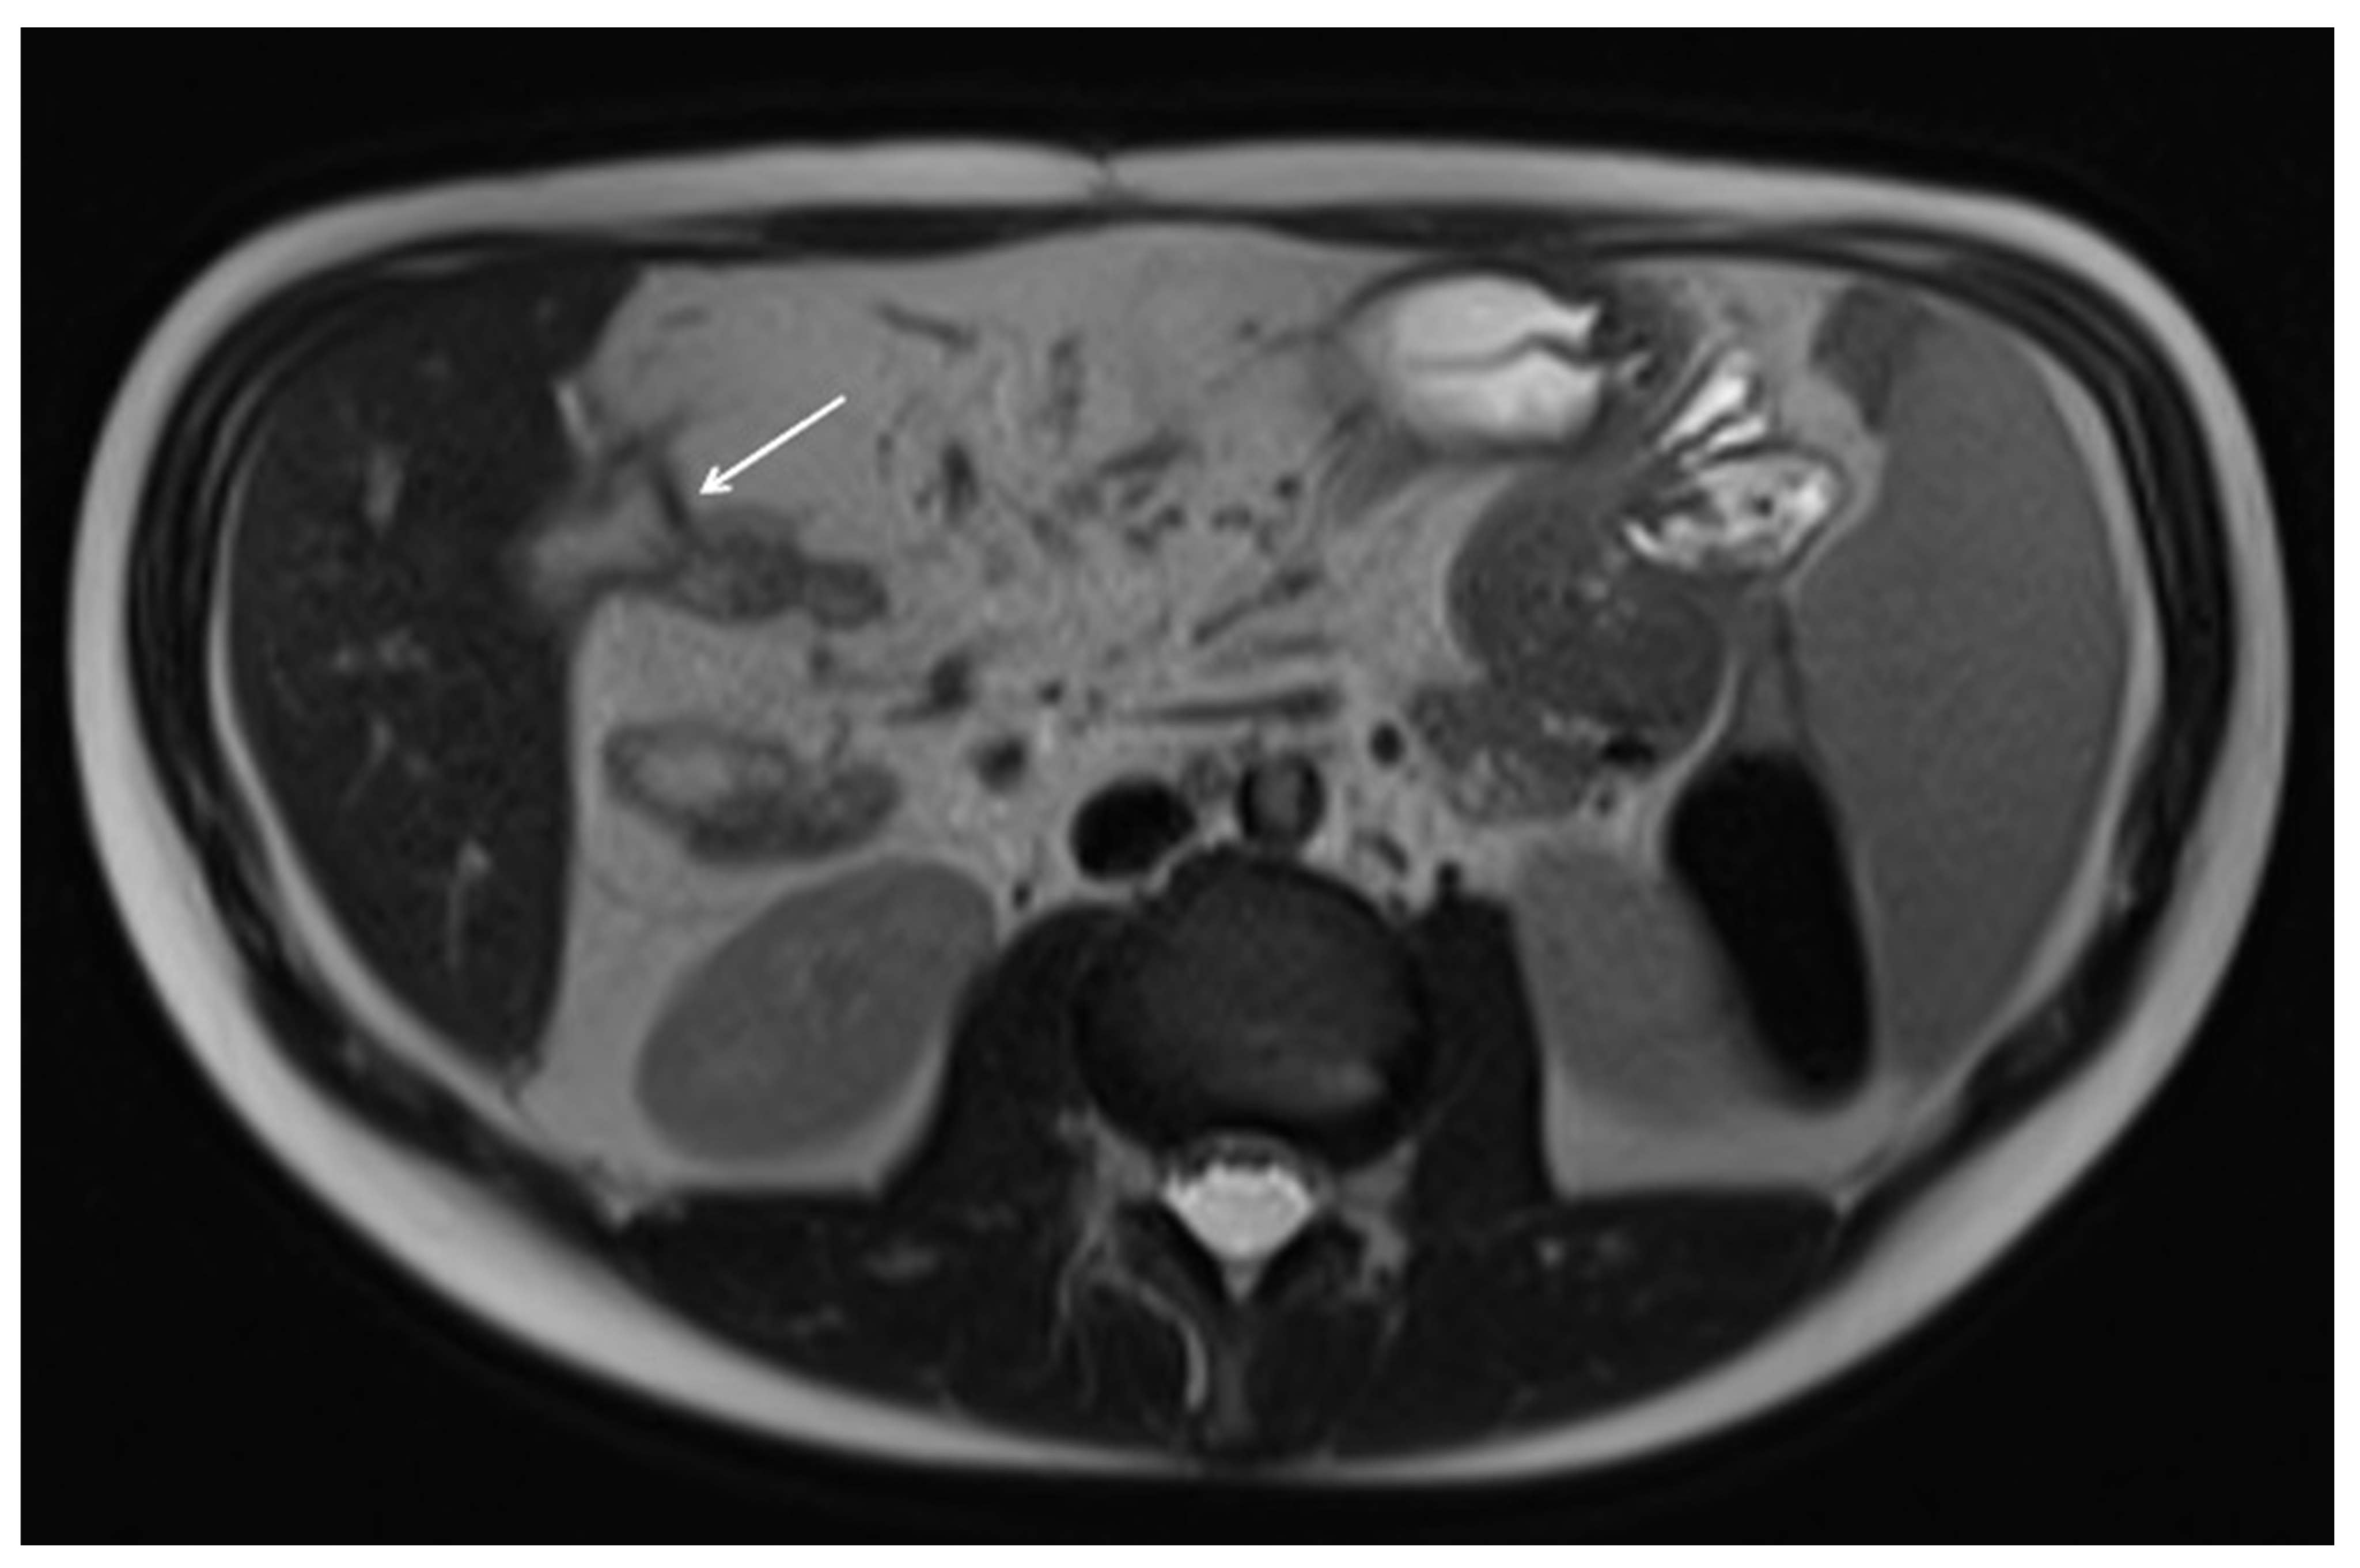

10. Imaging Findings Associated with Active CD Inflammation

11. Imaging Findings Associated with Penetrating CD Inflammation and Complications